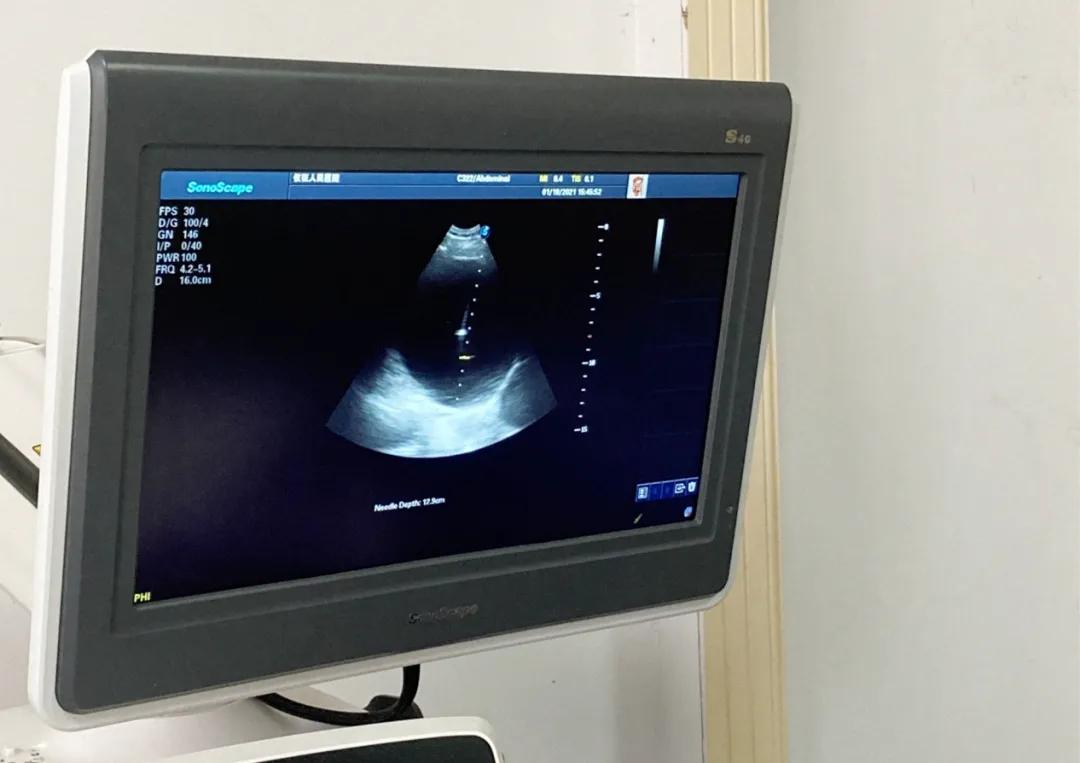

1月18日下午,仪征市人民医院超声科主任 方鸿 、 宫雪 等医师共同为一例巨大肝囊肿患者成功开展穿刺硬化治疗。

该患者男性,73岁,体检发现肝脏多发囊肿多年,因囊肿进行性增大。自述近期触及右侧腹部肿块并闷胀不适,来我院就诊。超声检查提示肝脏多发囊肿,右叶可见一巨大囊肿,几乎未见正常肝组织,大小约13.1x10.8cm。

(肝右叶巨大囊肿,几乎未见正常肝组织)

经常规术前检查,方鸿带领其团队在超声引导下为患者进行定位穿刺,缓慢抽吸囊液(囊肿较大,以防减压过快患者不适),共抽吸淡黄色液体750ml。抽吸后,巨大囊肿消失,随后注入硬化剂聚桂醇完成硬化治疗。术后,患者腹部不适症状明显缓解,观察30分钟无不良反应,自行回家。

首先彩超检查找到合适穿刺路径,彩超引导下进行局部浸润麻醉,在实时可视下把穿刺针精准进入囊肿内,开始抽吸囊液(绝大多数均为淡黄色啤酒样液体,少部分为褐色、淡咖啡色);囊液抽尽后根据囊液的量、囊液的性质注入硬化剂治疗。术后3个月、6个月复查,术后1个月囊肿可能处于回渗期,然后逐渐缩小至消失。